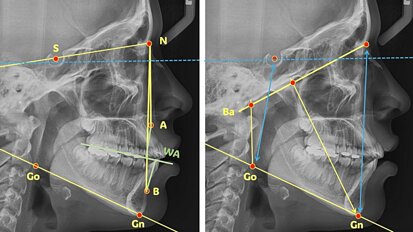

Los autores de este artículo, profesores en la Universidad de Santiago de Compostela, resaltan la relevancia del biotipo facial en el crecimiento, ...